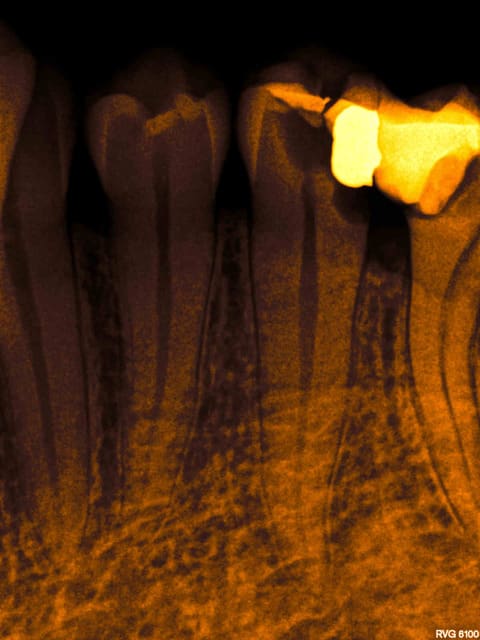

Post de depart !

Honnêtement, la dent est quand même bien niquée !

Fêlure mesiale et distale, le curetage n'est pas complet sur l'arrête restante.

Une couronne, c'est pas une connerie, patient 25-35 on tente l'onlay, patient 45-55, je couronne directement !

C'est une 6 ! 150 kg pression au cm2 !